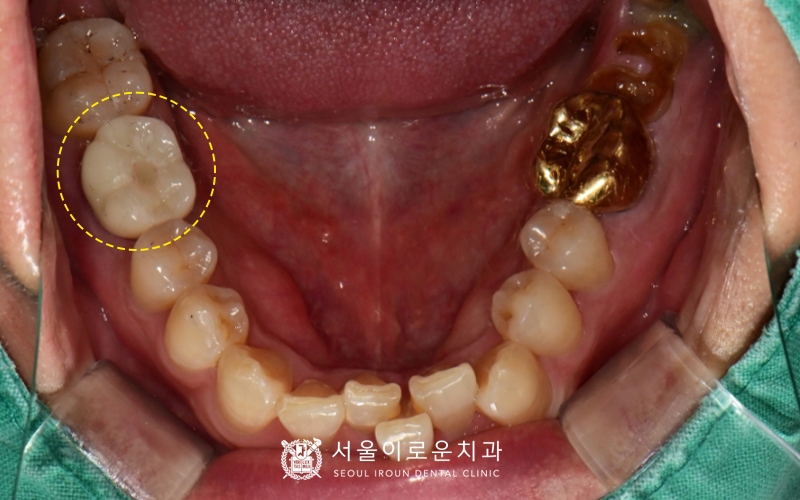

치료를 성공적으로 마친 뒤 촬영한

전반적인 구내 사진입니다.

처음 부천서울이로운치과로 내원하셨을 때와 비교하면

양쪽 아래 큰 어금니(#37,46)가

파절되어 제 기능을 하지 못하였는데

현재 임플란트를 통해 저작력을

보완할 수 있게 되었습니다~!

🦷치료 전>후🦷

또한, 통증이 있어 불편하셨던

왼쪽 위 큰어금니와 앞에 있던 치아는

각각 필요한 다른 치료를

진행함으로써 이를 뽑지 않고

치아보존을 위해 노력하였습니다. 😁